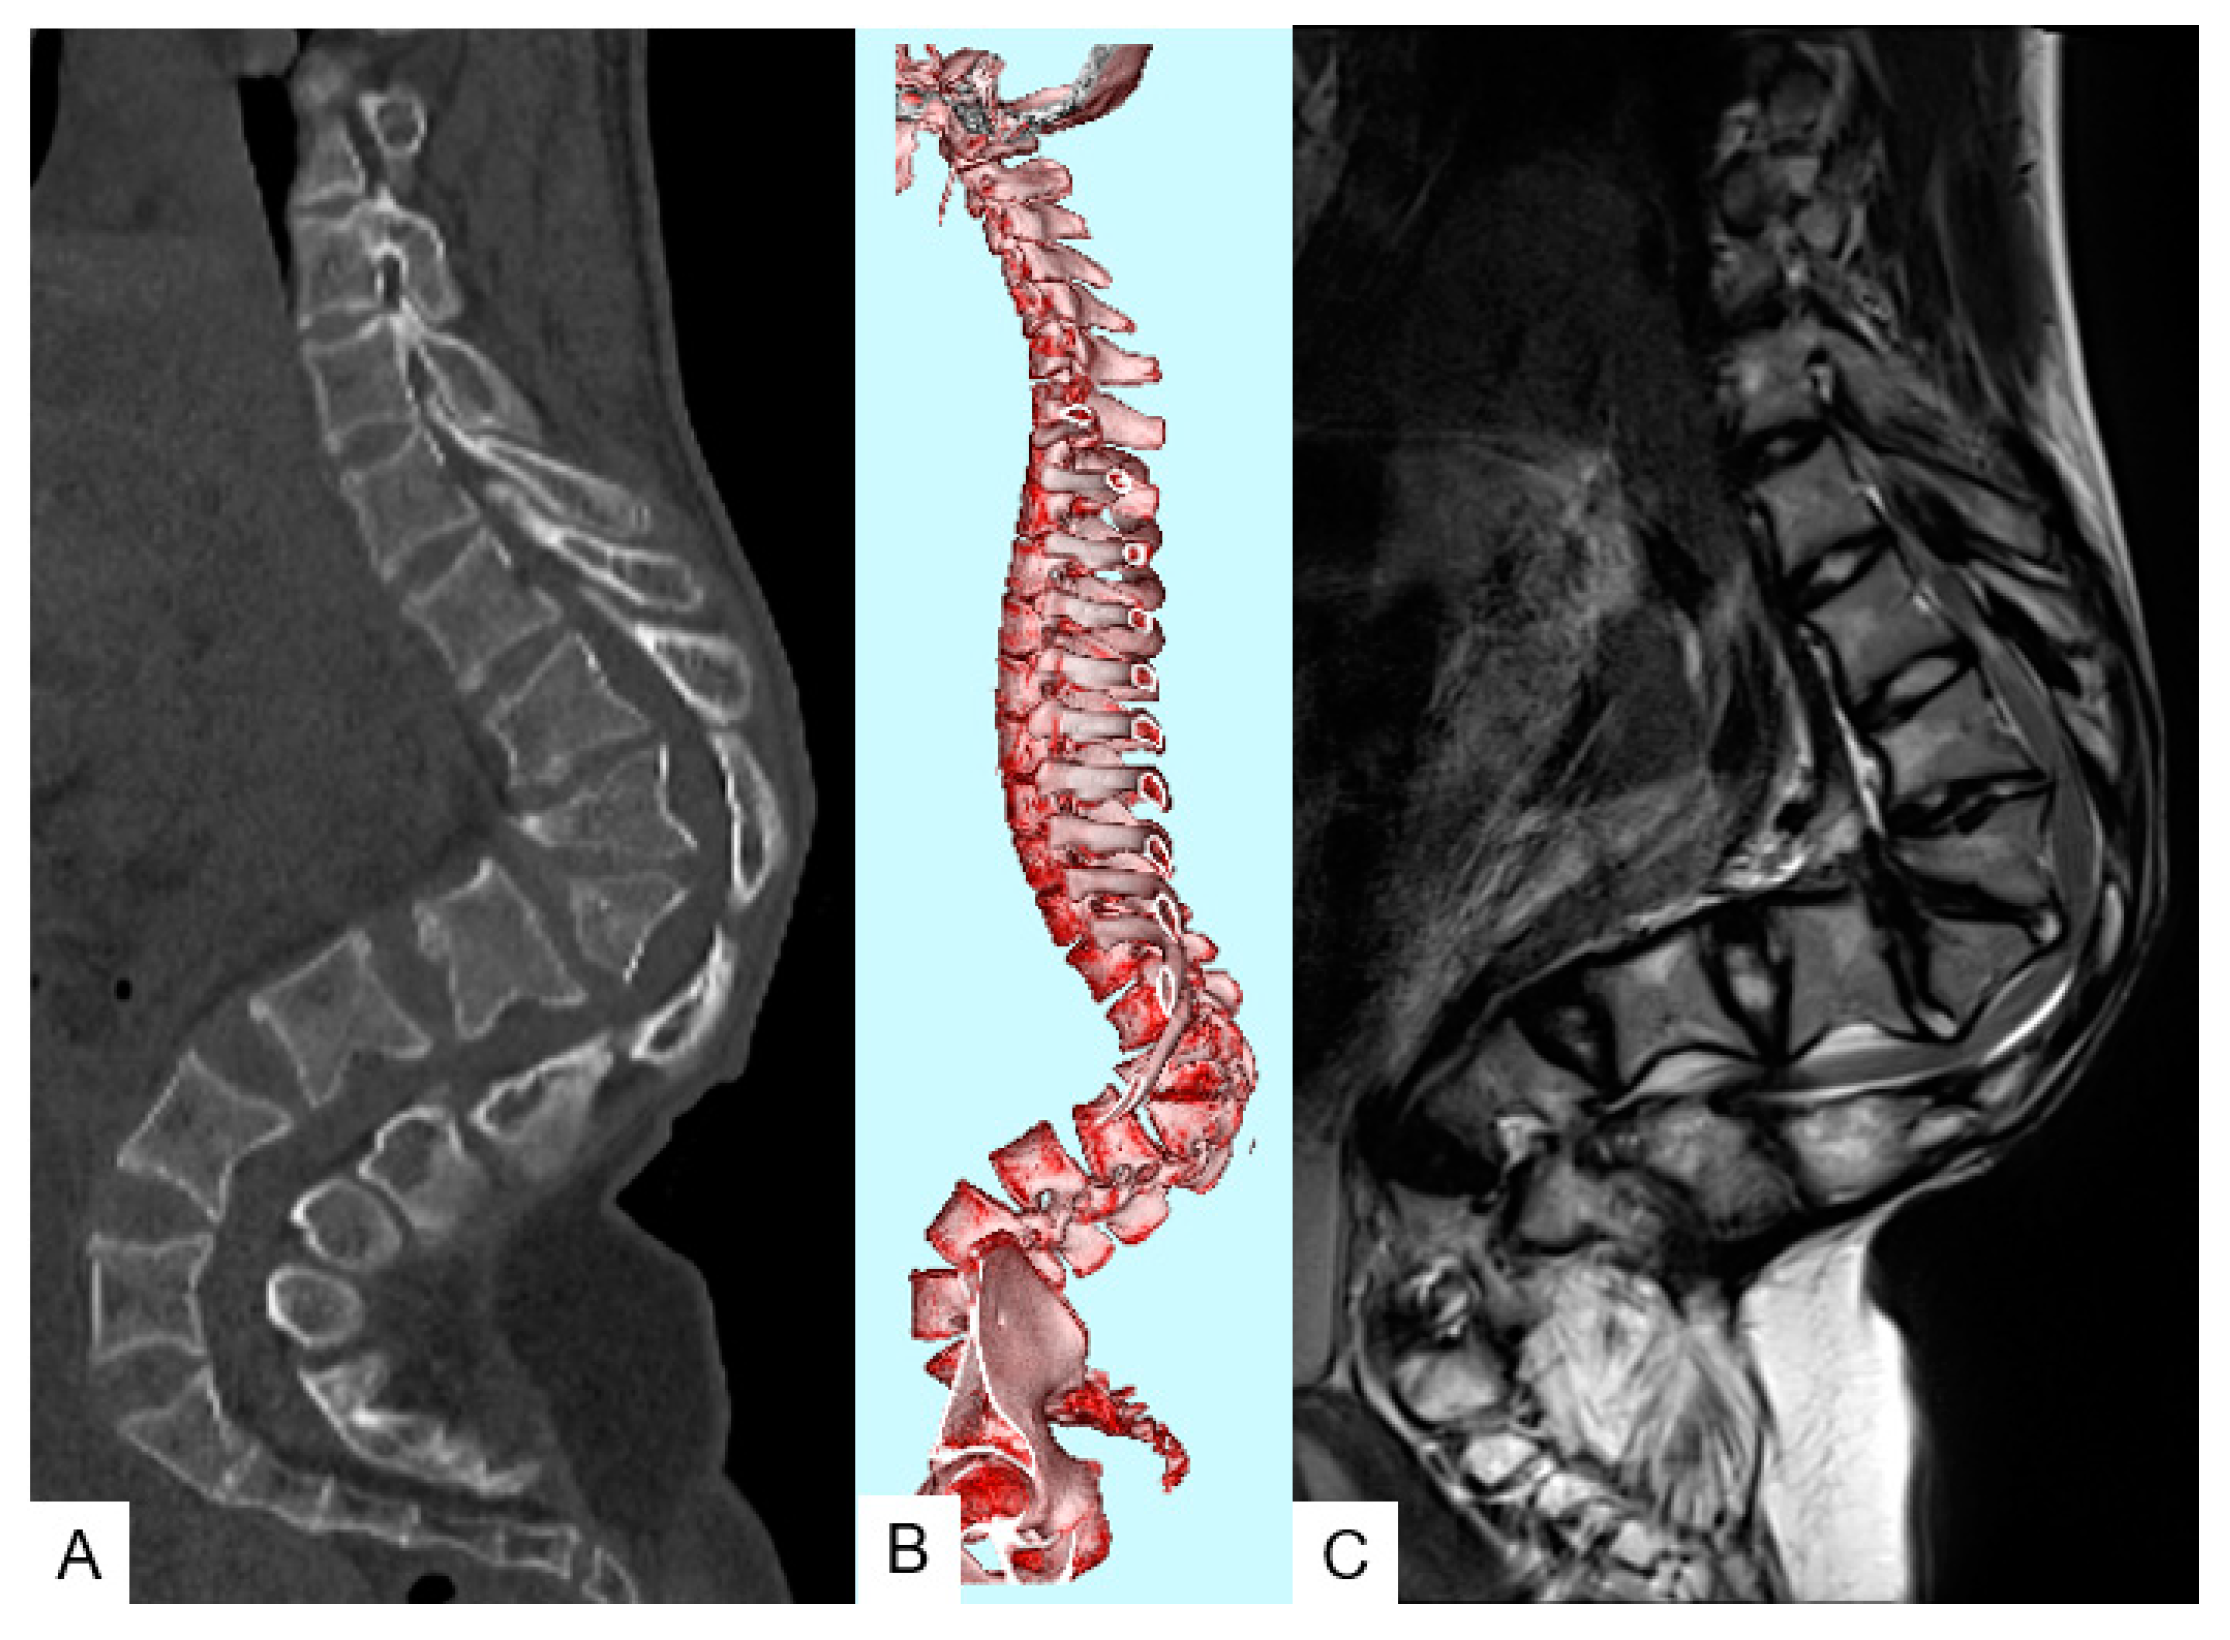

3.1. Case 1—16-Year-Old Girl, Achondroplasia, Thoracolumbar Kyphosis 126°

3.1.3. Preoperative Imaging

3.1.4. Surgery